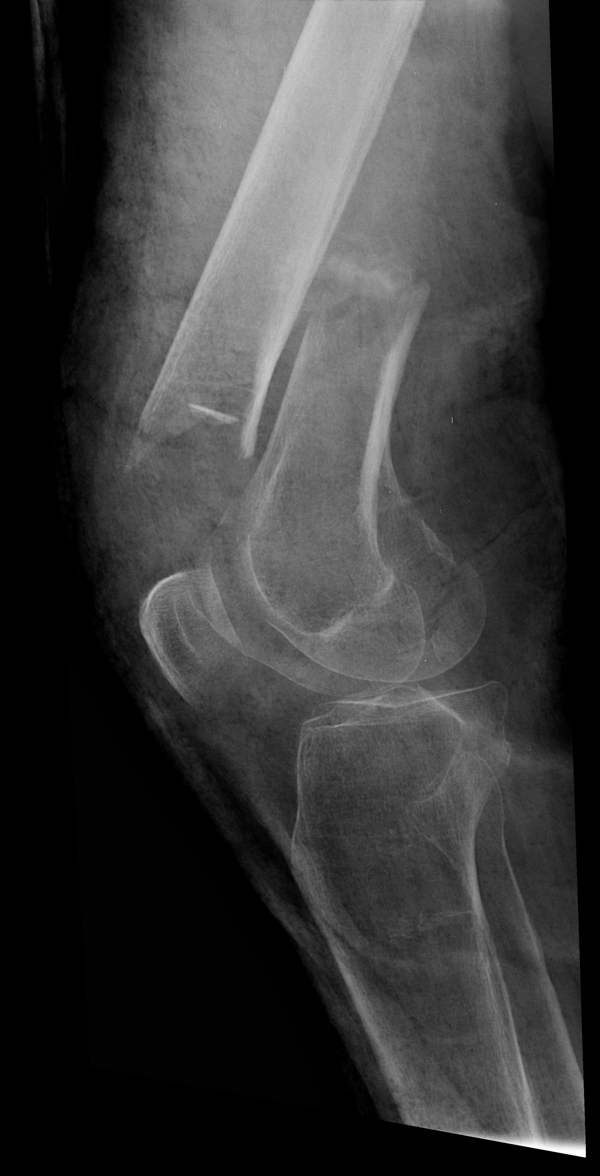

Решающее значение в установлении диагноза перелома шейки бедра имеет рентгенография тазобедренного сустава. У пожилых пациентов приведенные выше симптомы могут проявляться нечетко, а такие заболевания как инсульт или невропатия, вообще, не позволят поставить правильный диагноз без рентгена. Где сделать рентген? Перелом шейки бедра всегда сопровождается сильной болью, поэтому любые лишние движения оборачиваются новыми мучениями, а сопутствующие заболевания внутренних органов усугубляют ситуацию! Решение есть - воспользоваться уникальной услугой – цифровой рентген на дому. К вам приедет врач рентгенолог-травматолог, который выполнит весь комплекс лечебно-диагностических мероприятий и подробно расскажет, что делать дальше.

Получение качественных рентгеновских снимков на дому предъявляет серьёзные требования к рентгеновской аппаратуре. Далеко не каждый переносной рентгенаппарат позволяет получать снимки необходимого качества, чтобы достоверно поставить диагноз. Используемый нами рентгенаппарат АРА 110/160 в комплексе с компьютерным радиографом позволяет получать цифровые рентгеновские снимки высокого качества у пациентов различной комплекции и является уникальной услугой в Санкт-Петербурге, предоставляемой на дому.